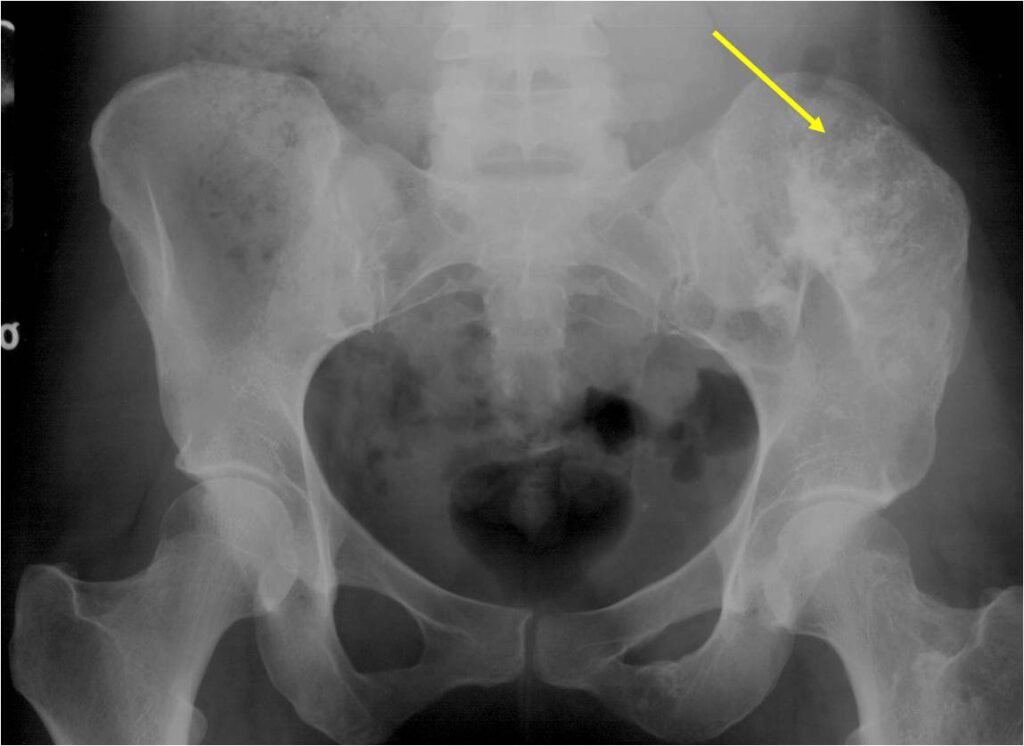

- Enchondromas of the pelvis, vertebrae and ribs are uncommon

- Almost all hyaline cartilage tumors of the pelvis are considered malignant based on anatomic location no matter what the pathology shows. These tumors will ultimately grow locally and have the potential to dedifferentiate or change into a higher grade chondrosarcoma.

- Localized, radiolucent defect usually with punctate calcifications

- Calcifications are stippled, punctate, popcorn like calcifications and “Ring and Arc” calcifications

- May be located centrally or eccentrically

- Most commonly found in metaphysis

- Geographic lytic lesion

- Central often metaphyseal in long bones

- Chondroid matrix with calcifications in majority of tumors